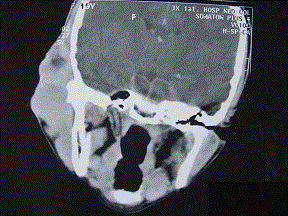

问题 19岁,女性患者,右侧面颊部肿胀一年,CT检查如图所示,请选择最佳答案 ( )

选项 A、右颊部横纹肌肉瘤 B、右颊部血肿 C、右颊部血管瘤 D、右颊部脂肪瘤 E、右颊部神经纤维瘤

答案 C